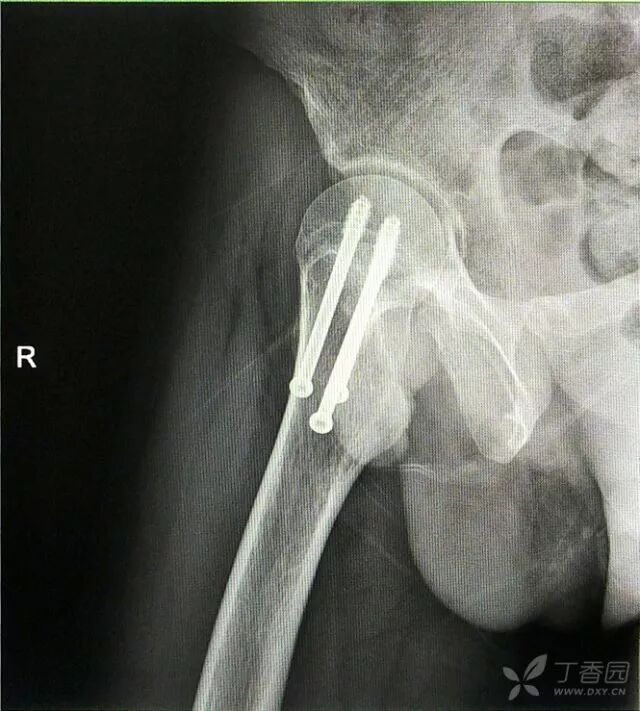

初步诊断:右股骨颈骨折(经颈型)

术后复查

术后十个月复查,骨折愈合,正常行走。